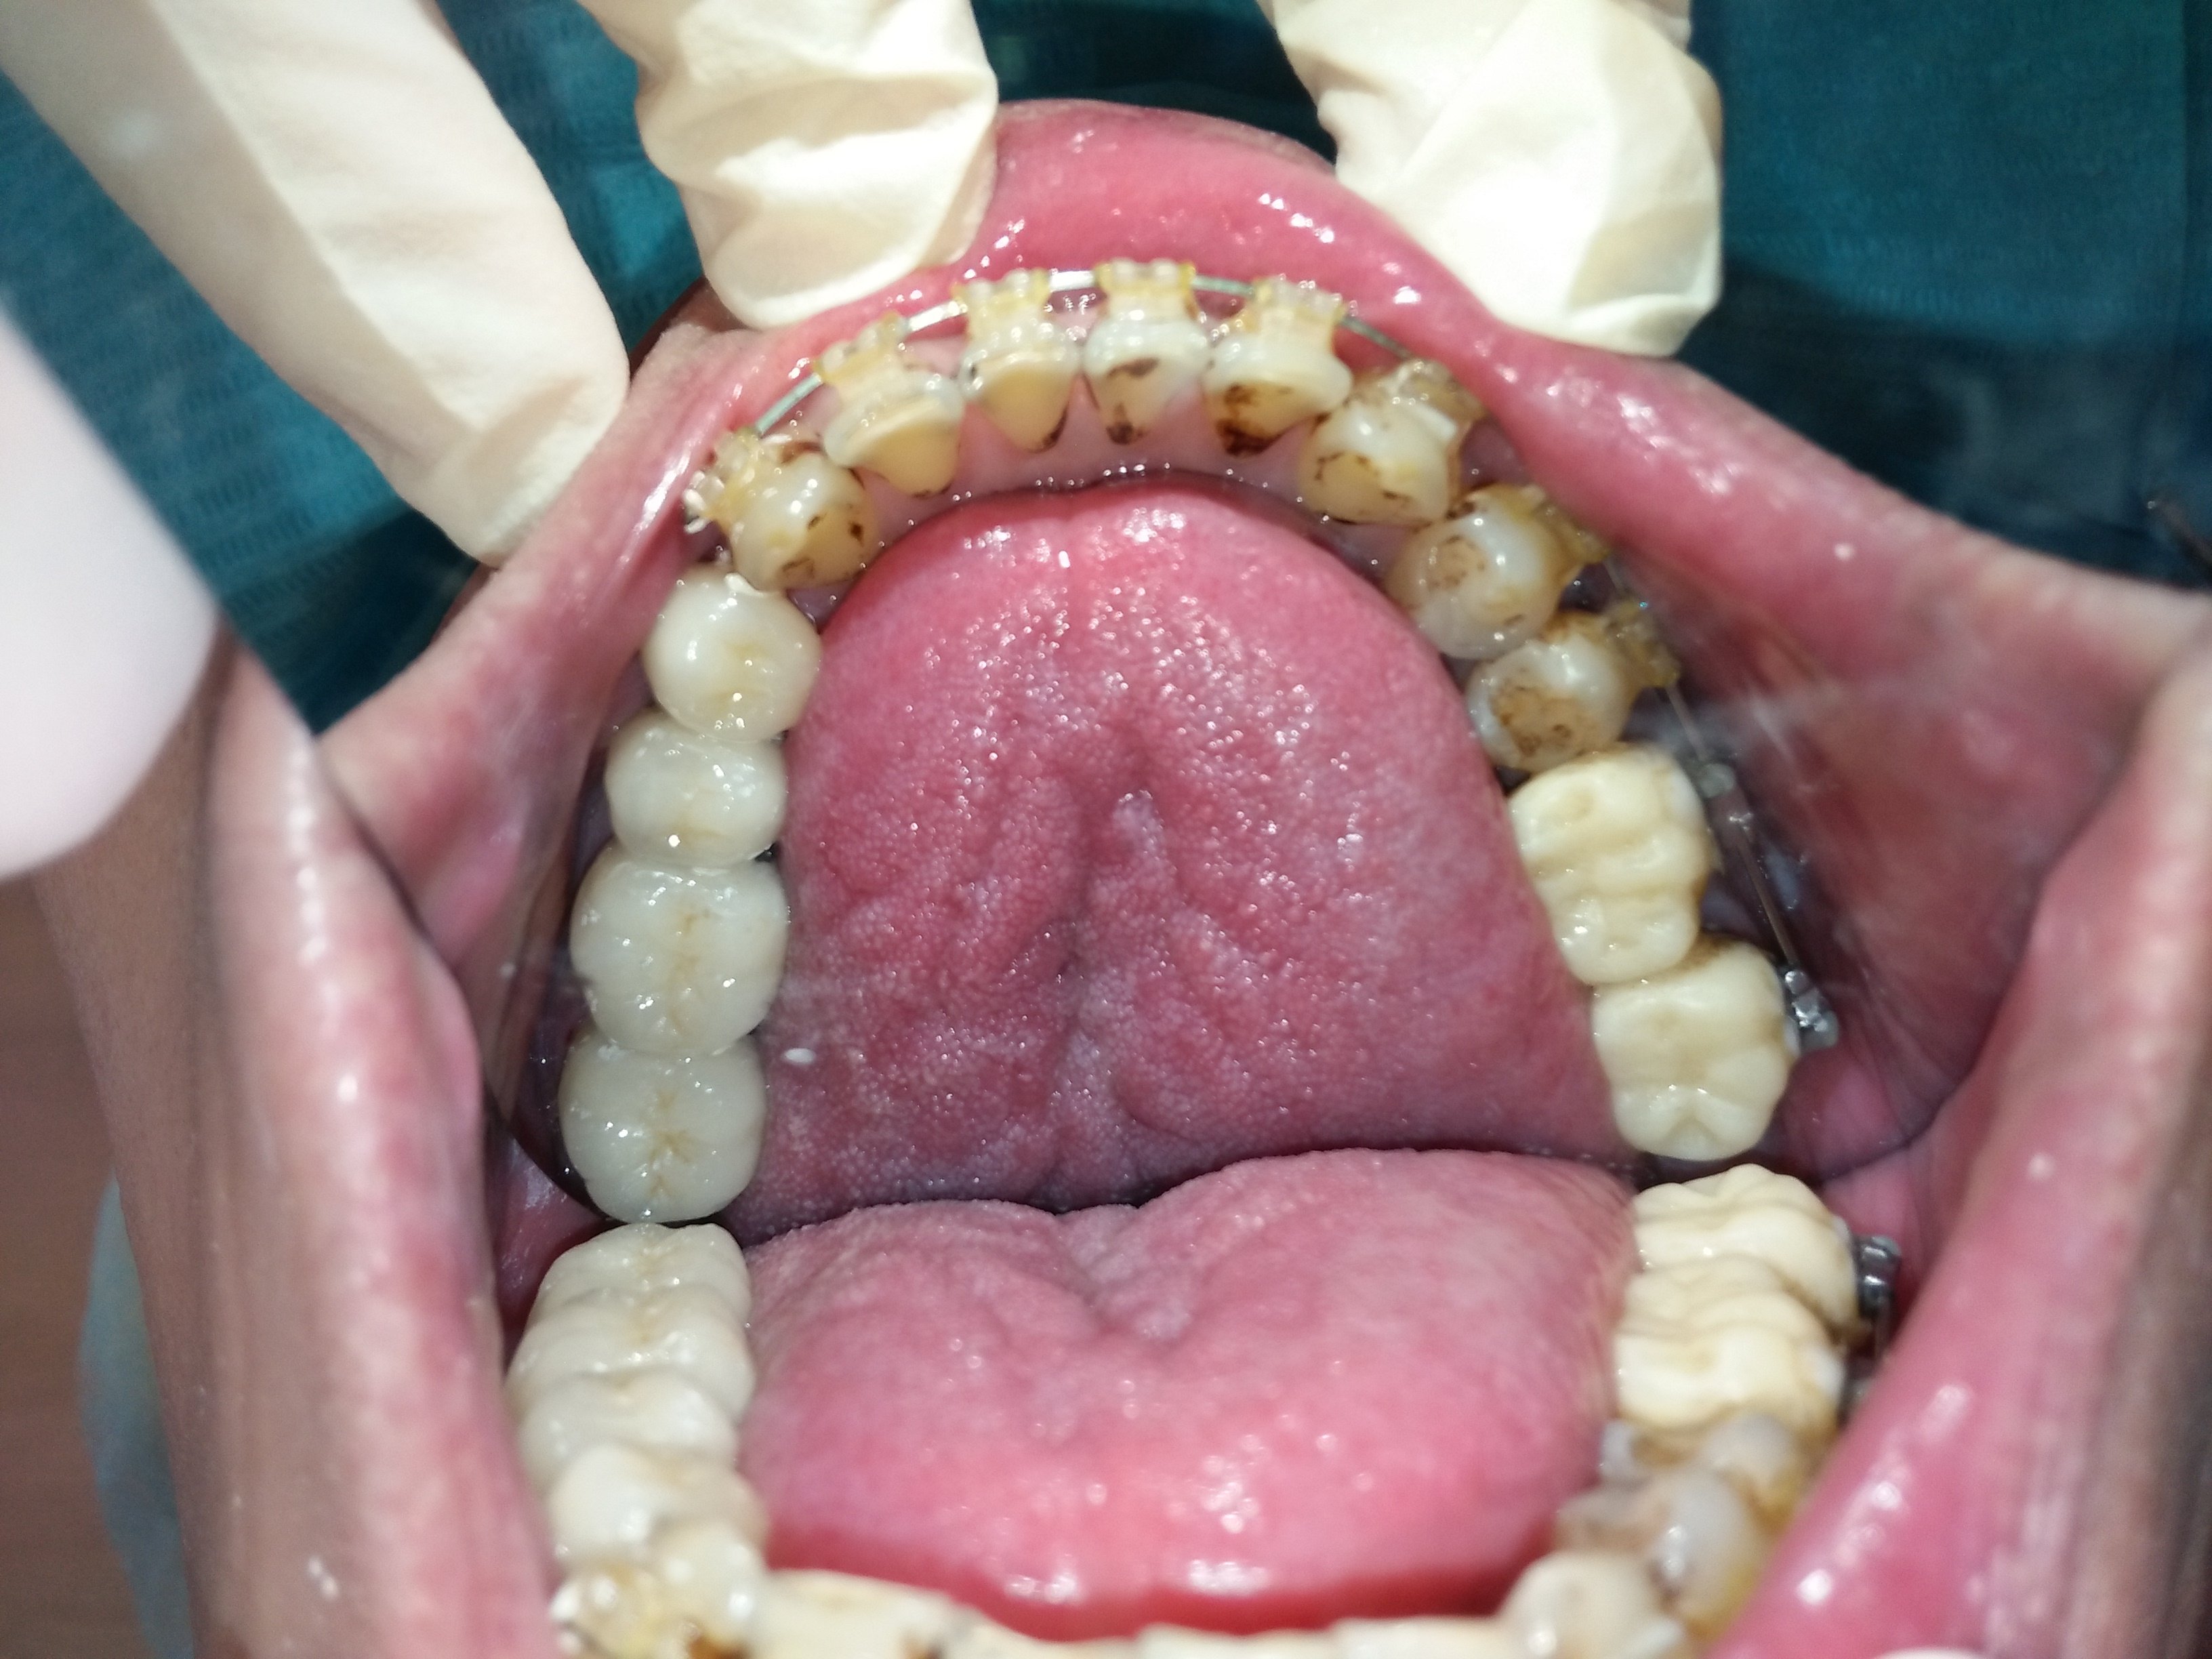

臨時的咀嚼一陣子並將咬合調順後,換成固定牙,更容易適應。

補骨後再植牙,讓牙齒地基有足夠的骨本,也讓自己擺脫總是在做假牙或做假牙的路上的命運。